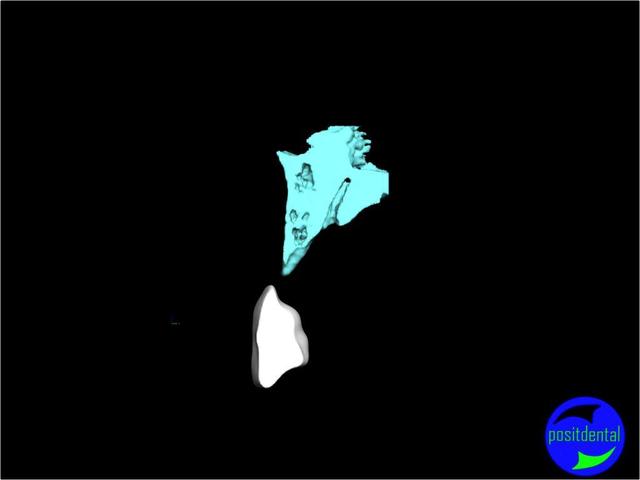

une autre vue du photshopman:

modèle stéréo du à la gentillesse de Posit